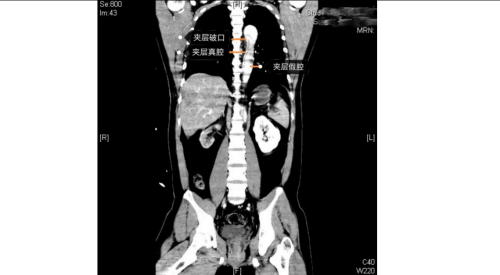

急诊科、麻醉手术科、外周血管介入科、急诊重症监护室等多学科团队火速响应。外周血管介入科主任、主任医师赵扬程及团队迅速评估患者病情并果断决定立即急诊手术。赵扬程指出,影像显示患者主动脉内膜严重撕裂,血流冲入血管壁形成巨大“假腔”。危急的是,夹层广泛累及腹腔主干血管,导致双下肢血管完全撕闭,下肢冰冷。此时主动脉壁薄如蝉翼,分秒间可致命破裂!同时,下肢及腹腔脏器严重缺血,如不迅速开通血管,将迅速引发肢体坏死、多器官衰竭。

手术室内,患者血压一度飙至惊人的320/150mmHg,循环濒临崩溃!麻醉团队全力稳定循环。在患者下肢几乎无法触摸到脉搏的极端条件下,外周血管介入科主任赵扬程及团队迎难而上,凭借精湛技术,精准置入支架,成功封堵主动脉内膜巨大破口,并精细重建了主动脉弓部受累的重要分支血管,恢复关键血流。这场持续近3小时的手术每一步都高风险且高度紧张,如同在死神面前进行“拆弹”。最终,这颗“血管炸弹”被成功拆除。